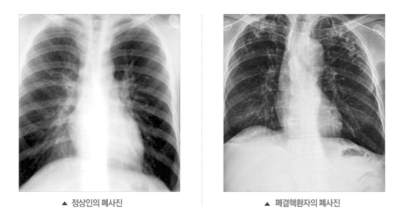

흉부 엑스레이

엑스레이 검사 방법으로는 실제 크기로 촬영하는 흉부 직접 촬영과 마이너스 70mm, 100mm 사진으로 촬영하는 간접 촬영이 있다고 하며, 일부 사람을 단체로 검사할 때 간접 촬영이 많이 활용돼요. 조사결과에 근거하면 결핵은 과감염성 결핵과 재활성성 결핵으로 구분되며, 기존 결핵은 소아결핵과 성인결핵으로 소속되는 경우가 많았어요. 인간면역결핍바이러스(HIV)에 감염된 사람들은 주로 과감염된 결핵을 보이 다고 알려져 있답니다.